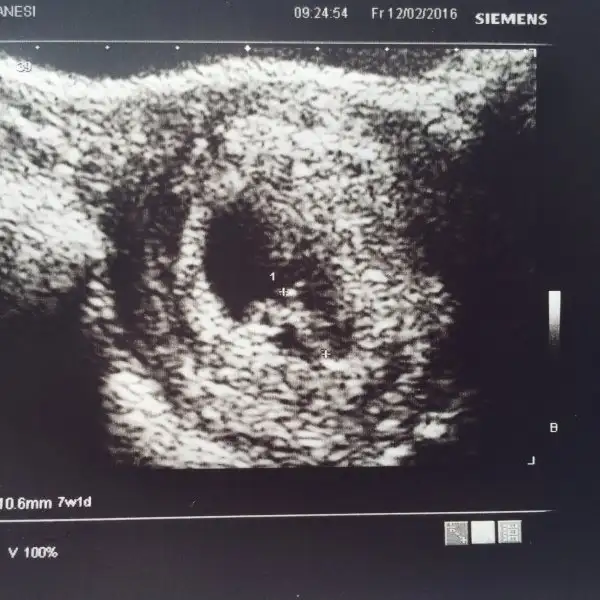

imaj ters mi düz mü yüklendi?Merhabalar benimde vajinal ultrason. 7+0 ama dr 6+1 gozukuyo gec dollenme dedi. Alabilirmiyim fikirleri

tamam düzmüş mm yazısından anladım. kız cnm ramziye göre....Merhabalar benimde vajinal ultrason. 7+0 ama dr 6+1 gozukuyo gec dollenme dedi. Alabilirmiyim fikirleri

Cnm 6 + larda daha iyi anliyorum burada solda bisey var yolk sac mi kordon mu cozemedim. Soldaki sey kordonsa erkek eger yolk sac ise kızdır. Bir hafta önceki foto var miMerhabalar ne kadar heyecan verici bir başlık.dayanamayıp üye oldum,bunca Zaman sadece okuyordum.benim karından 7+1 görüntüme ne denilecek merak ediyorum :)

Hayır Can'ım sadece bu var diğeri iki hafta önce idi sadece kese belli orada.yine de teşekkür ederim okurken Mutlu oldum.benim ilk bebeğim,yani erkek yada kız farketmez çünkü ikisi de yok:) teşekkür ederim yorumun için.zamanla görücez bakalımCnm 6 + larda daha iyi anliyorum burada solda bisey var yolk sac mi kordon mu cozemedim. Soldaki sey kordonsa erkek eger yolk sac ise kızdır. Bir hafta önceki foto var mi